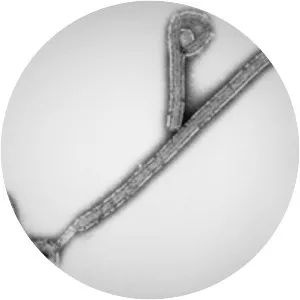

EBOV photograph

Scientific nameEbola virus

Higher classification Zaire ebolavirus

Zaire ebolavirus, more commonly known as simply Ebola virus, is one of six known species within the genus Ebolavirus. Four of the six known ebolaviruses, including EBOV, cause a severe and often fatal hemorrhagic fever in humans and other mammals, known as Ebola virus disease.